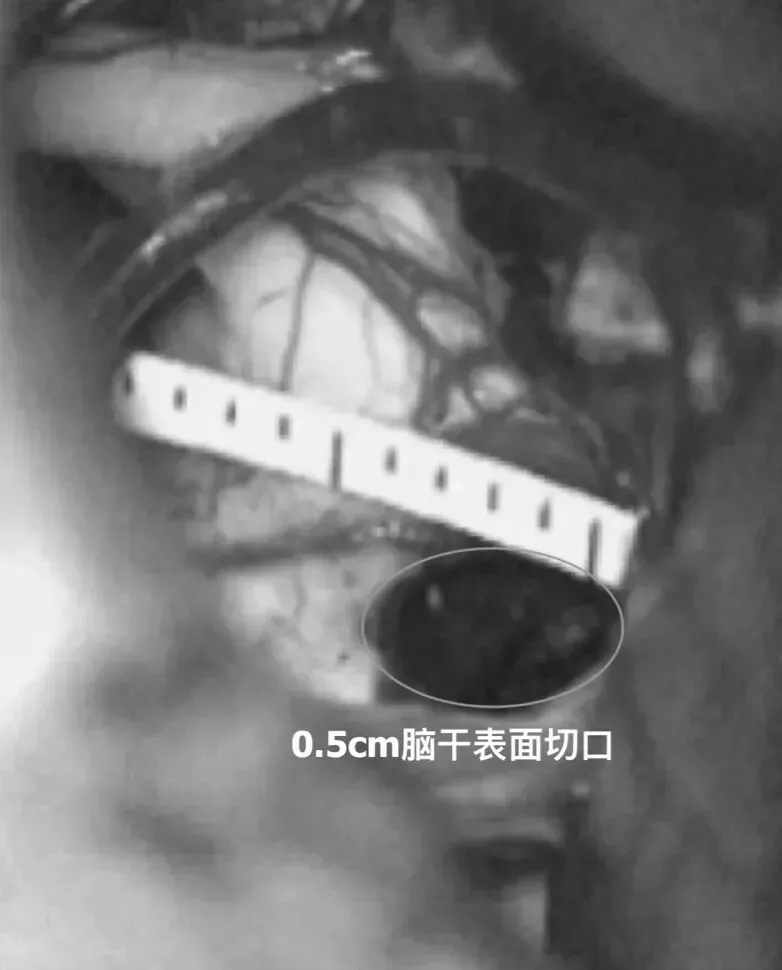

手术过程仅用了2.5小时,术后测量脑干切口仅3cm。

全切病变后,直尺测量经脑干切除病变切口为3cm